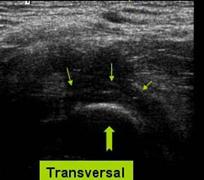

Sectiune transversala la nivelul santului epitrohleo olecranian

Nervul ulnar normal, cot in extensie →

Luxatie anterioara a nervului ulnar in flexia cotului →